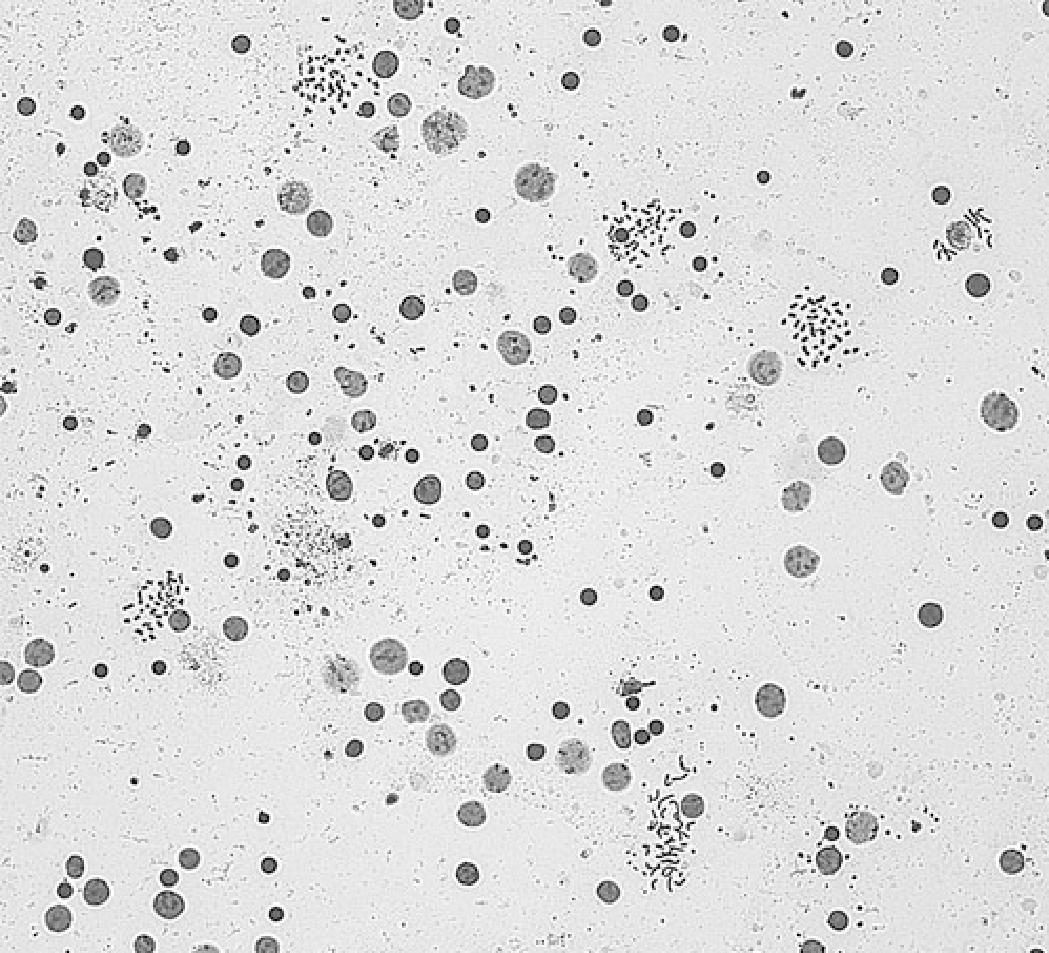

Densidad esperada de células y metafases (magnificación 125x) Tomado de Wan, T S (2017) Cancer Cytogenetics Springer New York,(p 39)